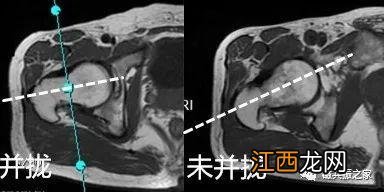

单侧髋关节笔画的扫描时,采用脚尖并拢的方式扫描更有利于斜冠状x和斜矢状的定位,且可以有效避免定位角度大于45°后出现图像反转的情况 。